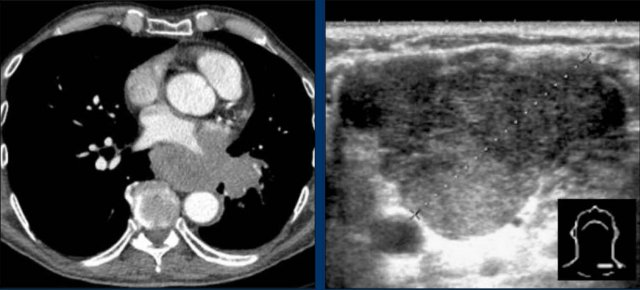

CT Imaging

• Contrast-enhanced CT shows bulky subcarinal lymphadenopathy displacing the azygoesophageal recess and compressing the left atrium.

• Biopsy of a cervical node confirmed small cell lung carcinoma.

Continue with PET-CT...

PET Imaging

• PET-CT demonstrates extensive hypermetabolic lymphadenopathy in the mediastinum and neck, which is more conspicuous than on chest radiography.

• Cervical lymph nodes are involved—an important finding as they are accessible for biopsy.

Continue with images of CT and ultrasound...